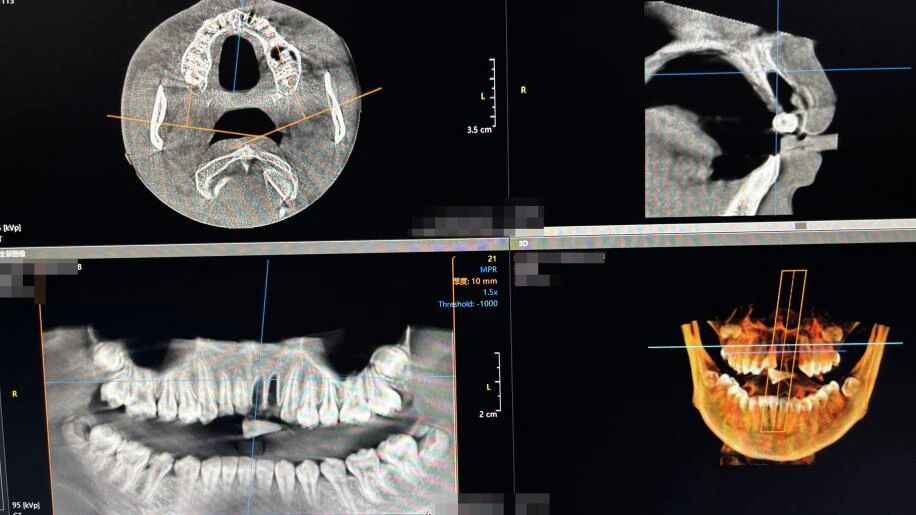

术前CBCT影像检查